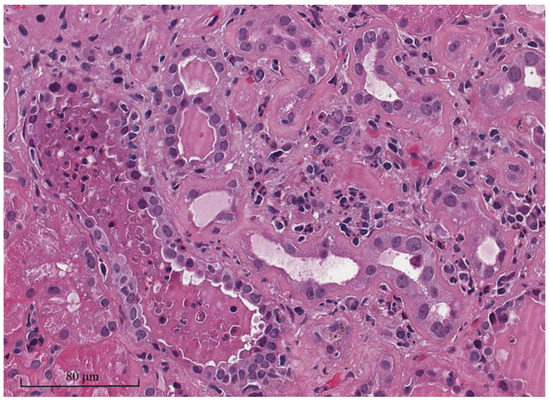

| CMV nephritis | Rare (approximately 0.2% of KTR). | Allograft dysfunction, fever, diarrhea, leukopenia, presence of high level CMV viremia or CMV disease in other organs such as pneumonitis, hepatitis, or colitis. | Mononuclear interstitial inflammation, typical peri-nuclear halo (owl’s eye) inclusion, viral inclusion in both nuclei and cytoplasm, viral cytopathic change in glomeruli (infected endothelial cells), 150–200 nm viral particle from EM. | Ganciclovir or valganciclovir are the first-line treatment, with a reduction in immunosuppressive medications. Foscarnet or cidofovir are used for drug resistant CMV infection. |

| Adenovirus nephritis | Rare (true incidence is unknown, probably less than 0.5% of KTR). | Allograft dysfunction, fever, gross or microscopic hematuria, can present with systemic involvement such as hemorrhagic cystitis, pneumonia, hepatitis. | Marked tubular necrosis and interstitial inflammation with mononuclear cell infiltration, mimicking cortical necrosis, hemorrhagic interstitial nephritis, granuloma formation, viral nuclear inclusion changes, and 70–80 nm viral particle from EM. | Immunosuppressive medication reduction is the mainstay treatment. Second-line treatments include IVIG or cidofovir. |